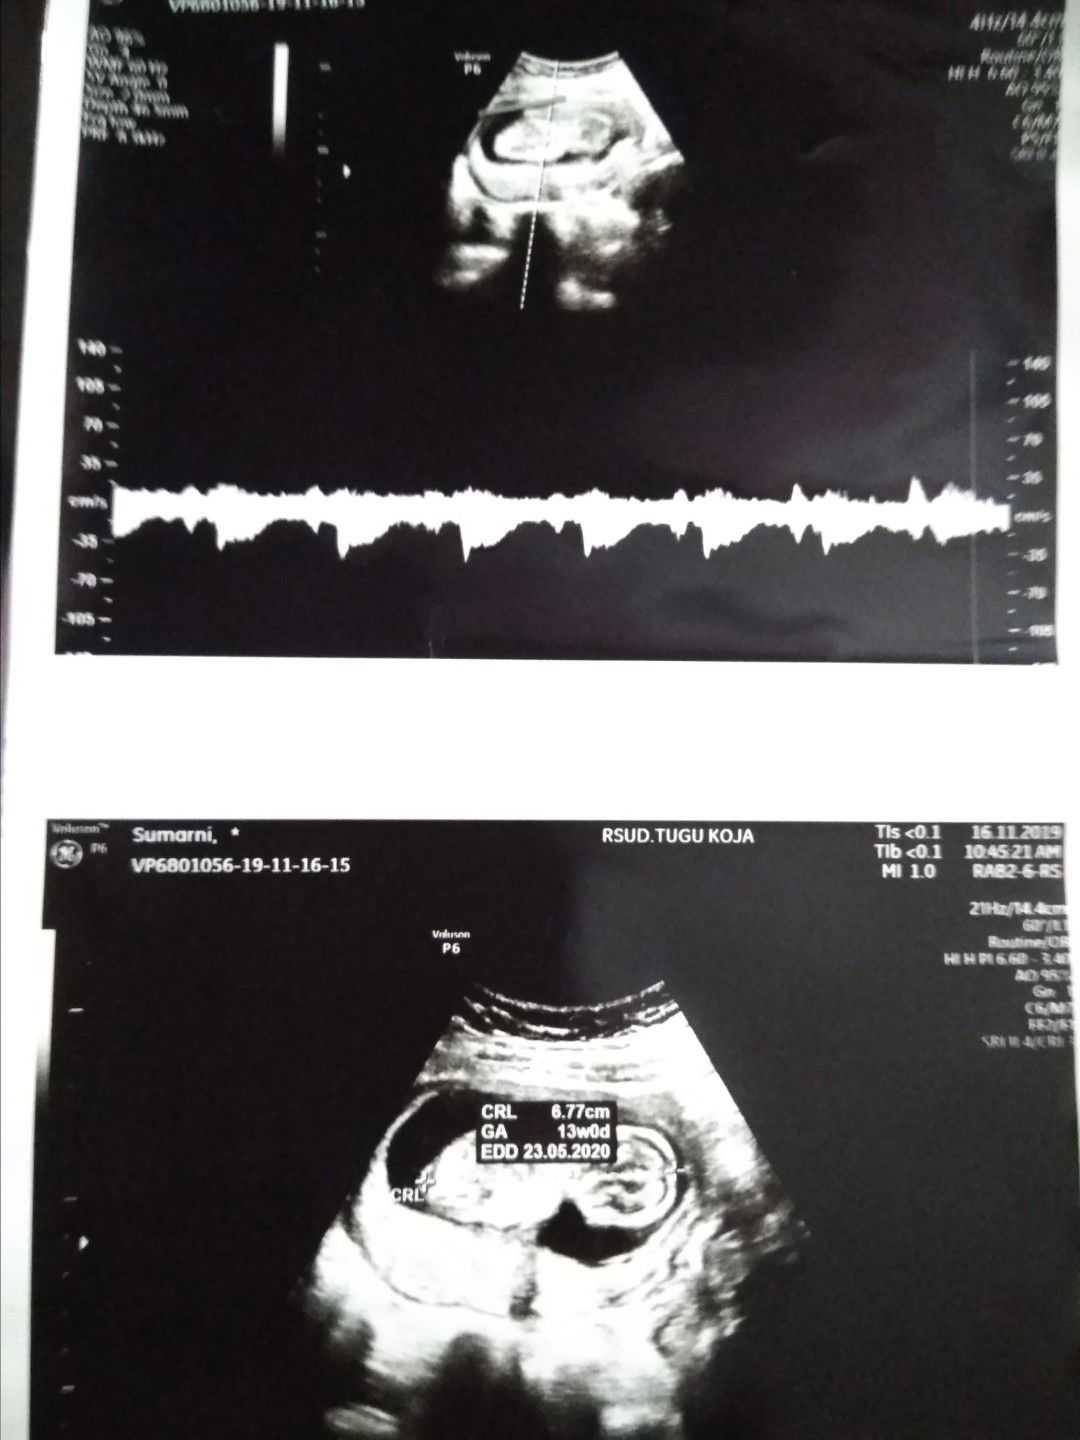

hasil USG.

Alhamdulillah semua dlm keadaan baik, SeHaT selalu ya sayang, Kakak mu selalu bertanya kpn Dede nya keluar ?